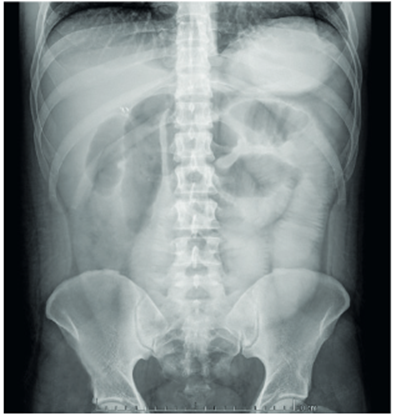

Por lo anterior, el paciente fue diagnosticado con obstrucción intestinal por adherencias y se realizó una liberación de adherencias por laparoscopia. En el posoperatorio, el paciente se mantuvo con débitos altos por la sonda nasogástrica, por lo que al quinto día se solicitó un tránsito intestinal con gastrografina, sin existir progresión del contraste en el intestino delgado, con falta de vaciamiento gástrico (Figura 2).